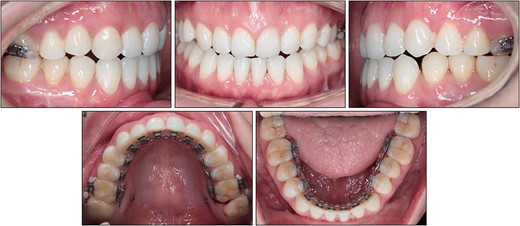

After treatment, class I canine and molar relationships were obtained on both sides with a normal overjet and positive overbite (Fig. 5). The posttreatment lateral cephalometric evaluation showed an improvement in both anteroposterior (point A-nasion-point B angle, 3.1°) and vertical dimensions (Frankfort mandibular angle, 31.0°). The posttreatment panoramic radiograph showed adequate root parallelism without any sign of root resorption (Fig. 6). The lateral cephalometric superimpositions confirmed the intrusion of the maxillary molars, the extrusions of the incisors, and the counter-clockwise autorotation of the mandible (Fig. 7).

Bonded lingual retainers were placed in both arches along with clear retainers for night-time use. The patient was evaluated at a 2-year follow-up and the treatment results remained stable (Fig. 8). The patient expressed satisfaction with the treatment, citing both the resolution of the chief complaint and the invisible nature of the appliances.